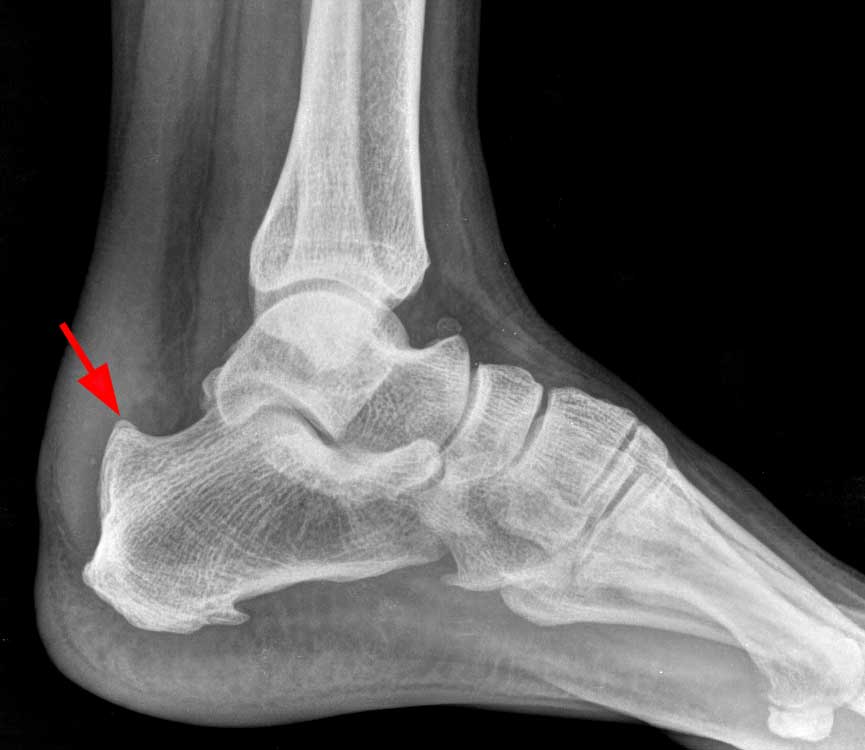

Pour l'expression courante, voir talon d'achille. Calcification of the achilles tendon. It is estimated that three to five percent of people suffer from this disorder 'calcifying' refers to calcium spots and 'rotator cuff' to the four muscles that together form the shoulder belt.

On peut également rechercher des calcifications qui témoignent d'évolution chronique de la. What is calcification at the insertion site of the achilles tendon answered by dr. Quand le calcium s'accumule dans le tendon.

La tendinite calcifiante fait référence à une accumulation de calcium dans la coiffe des rotateurs (calcification). Tendon calcification occurs mainly in the tendons around the shoulder head. Pour l'expression courante, voir talon d'achille.